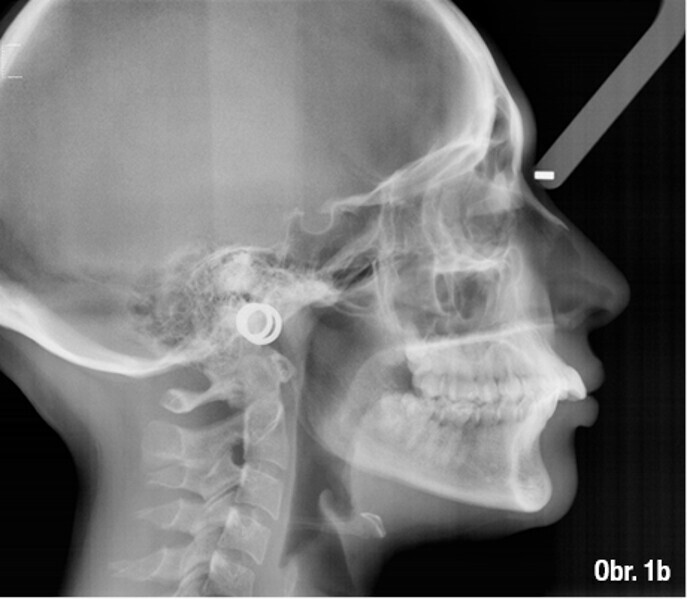

Distalizace horních molárů pomocí alignerů a cyklických sil